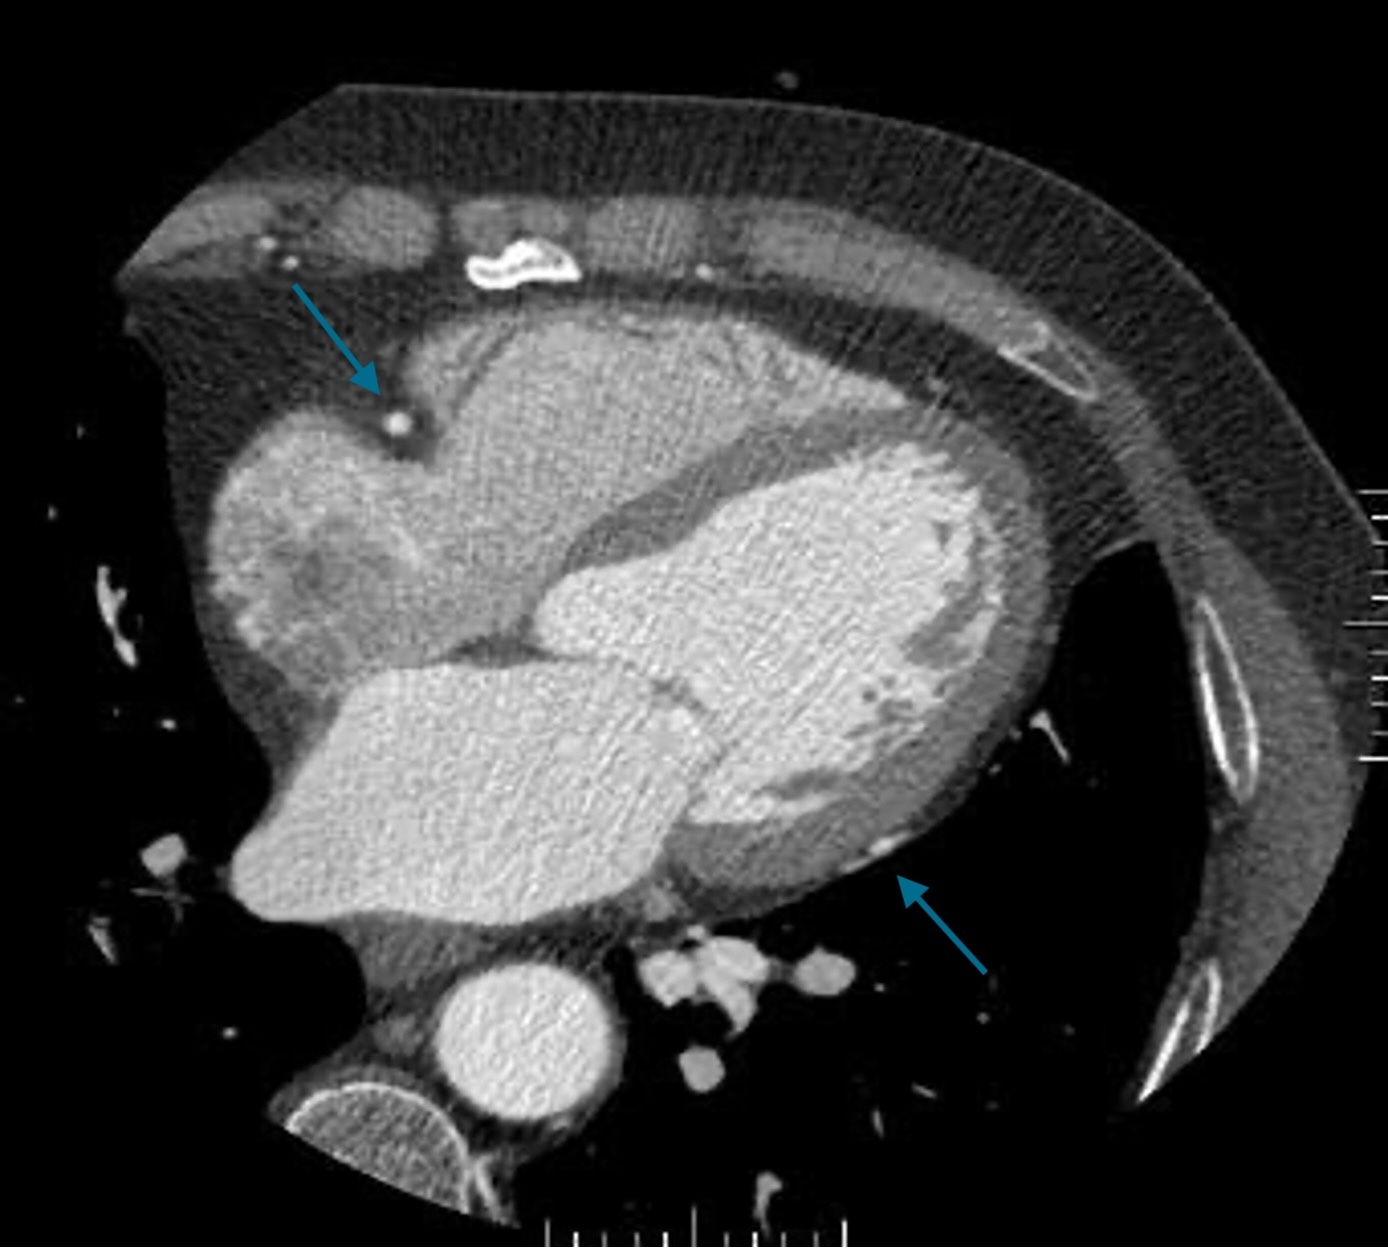

Kardio-CT: Tipps für eine erfolgreiche Herzbildgebung und häufige Fehler, die Sie vermeiden sollten – unabhängig an welchem System

Von Katrin Hägele – Ihre Expertin für moderne Bildgebungssysteme